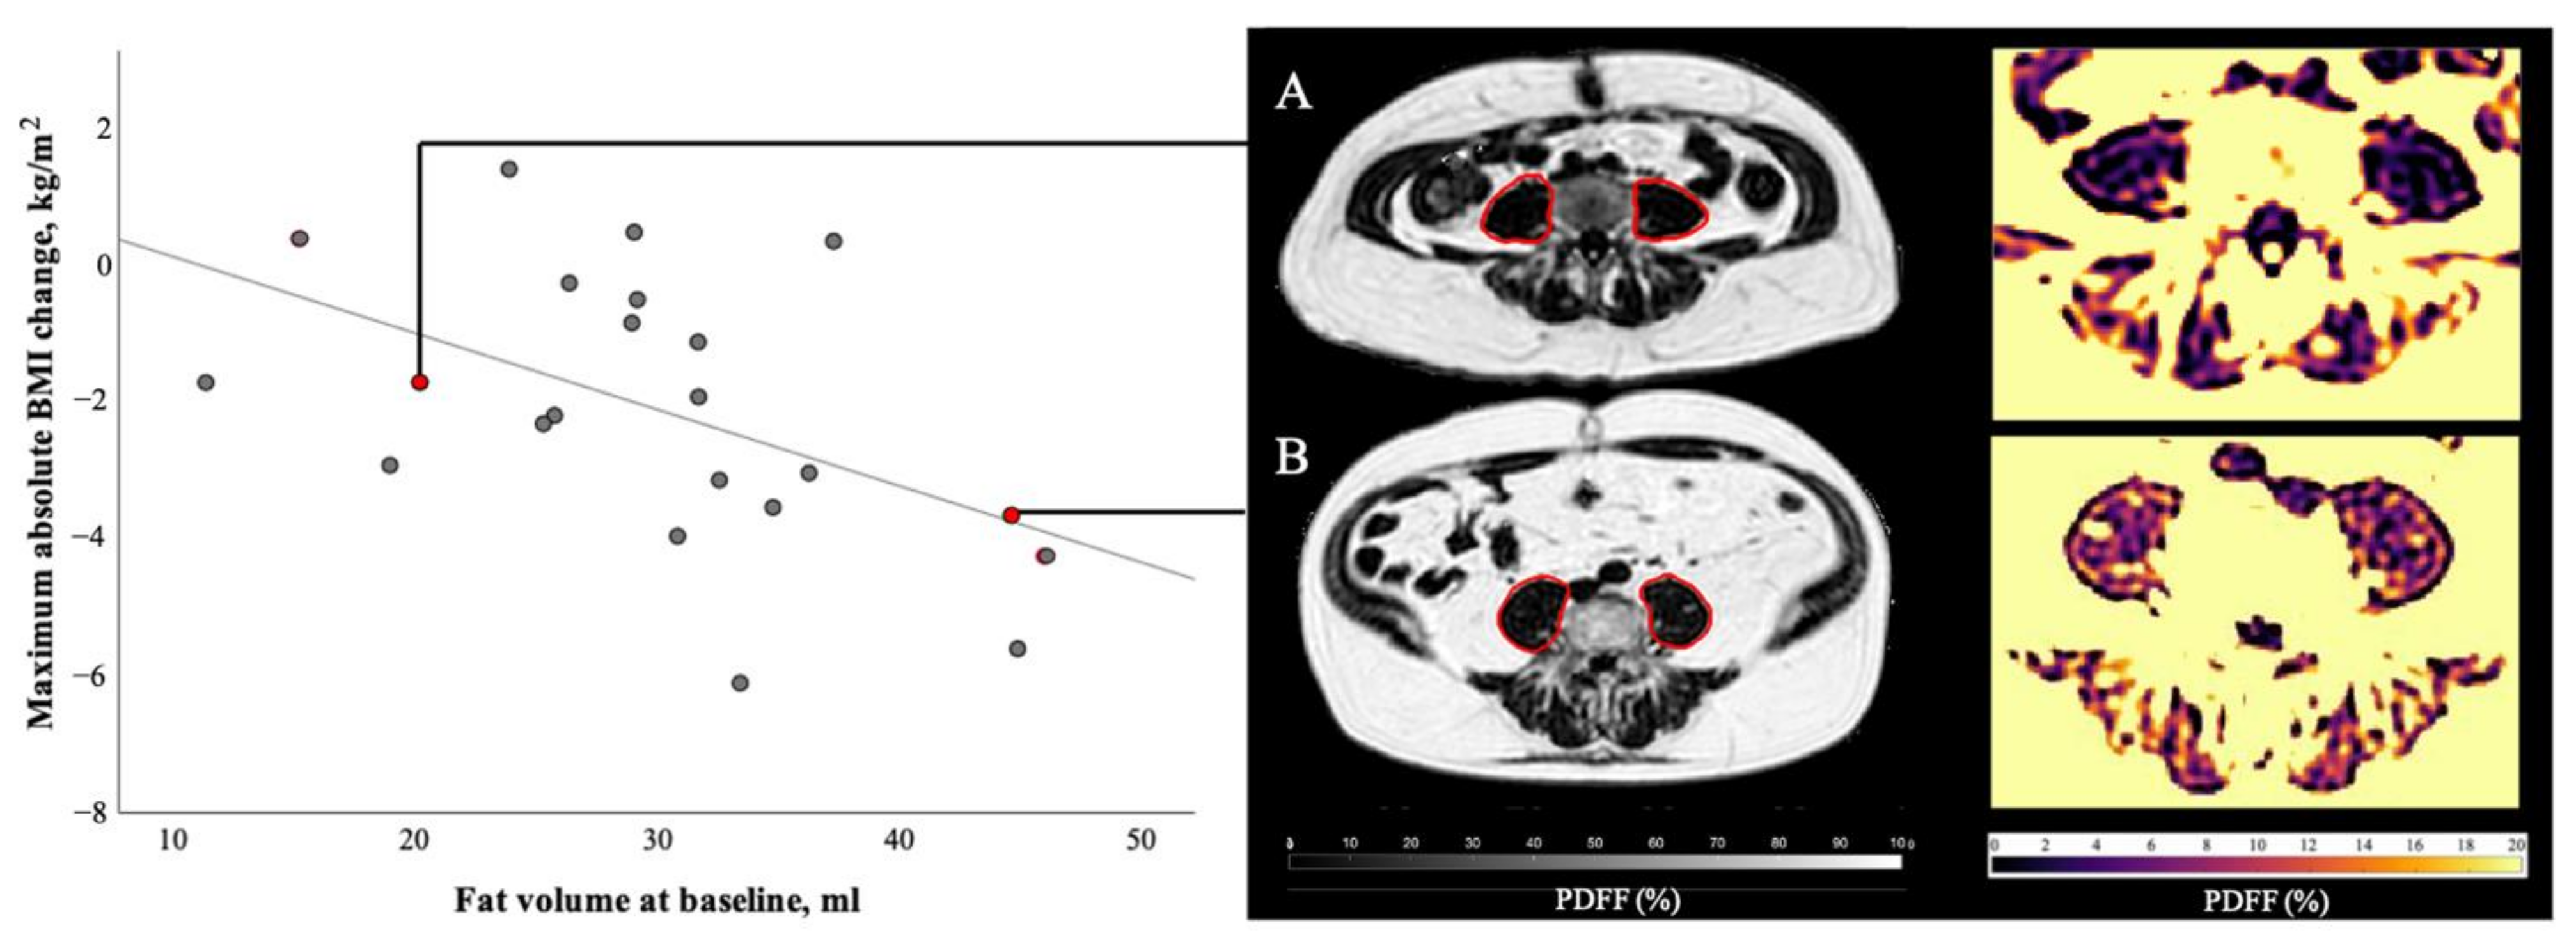

Figure 5.

Correlation of psoas muscle fat volume at baseline and maximum absolute BMI change during the course of disease. At baseline patient A (female, 48 years old, BMI 26.2 kg/m2, suffering from colorectal cancer) presented with 20.2 mL of psoas muscle fat volume, patient B (male, 64 years old, BMI 33.1 kg/m2, suffering from ductal adenocarcinoma of the pancreas) with 44.6 mL of psoas muscle fat volume. During the course of this study, patient A lost 1.7 BMI points and patient B lost 3.7 BMI points. Statistical analysis of all 22 patients with follow-ups revealed a significant correlation (r = −0.51, p = 0.02) between baseline psoas fat volume and maximum BMI change during follow-ups.